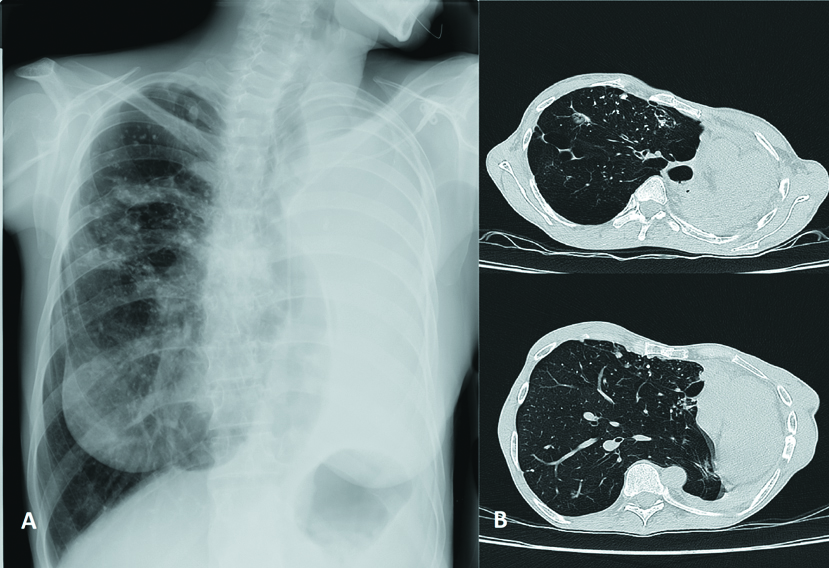

Upon admission (25.03.2021), X-ray and CT of the chest organs were performed (Fig. 1).

Figure 1. X-Ray (A) and CT of the chest organs (B) at admission, where A – displacement of the mediastinal organs (trachea, heart) to the left; B – large upper anterior pulmonary hernia, large foсus in S2 of the right lung, destroyed left lung.

The study of the X-ray and CT of the chest organs on admission revealed the following: the left lung is considerably smaller in volume, airless parenchyma, visualized lumen of the bronchi. The multilocular air cavity of the pleural empyema is located in the posterior costal section on the level of fourth to eleventh ribs, with low level of fluid and multiple small bronchopleural fistulas. On the left at the level of the second intercostal space, an encysted air cavity (size: 1.8х1.4х2.4 cm) with fluid. The mediastinum organs are shifted to the left and rotated. In the right lung, overexpanded for compensation, there are scattered multiple tuberculomae and dense partially calcific loci of various sizes. Probable presence of a small destructive air cavity in the shallow tuberculema located in the S5 under the pleura along the left parasternal line. Pulmonary mediastinal hernias are visualized: anterior superior up to the left anterior axillary line, left posterior in the section between the left paravertebral and scapular line. The volume (V3) of the hernia of the anterior mediastinum of the right lung is 740.65 cm3, and of the hernia of the posteroinferior mediastinum, 379.97 cm3. Conclusion: CT signs of pleural empyema on the left with bronchopleural fistulas, multiple tuberculomae of the right lung. Mediastinal pulmonary hernias of the right lung (Fig. 1).